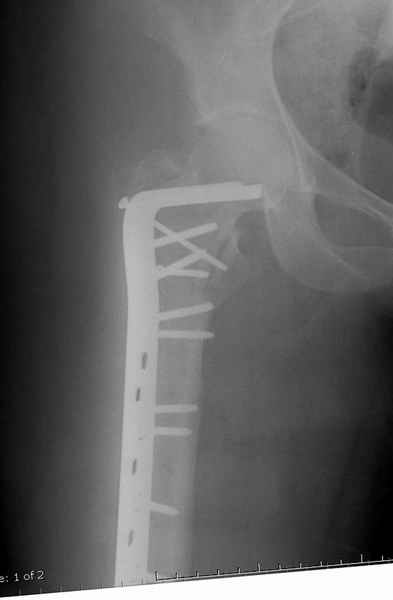

Это 4-фрагментный перелом, традиционно-современная фиксация - это динамический бедренный винт, DHS. Либо какой-либо из проксимальных бедренных гвоздей, предназначенных для ранней полной нагрузки, из-за меньшего доступа, других преимуществ перед DHS нет. Если доступен только реконструкционный гвоздь, то винты вводить надо очень точно и аккуратно субхондрально, т.е. максимальной длины, а то прорежутся в головке.

Вот пример наших американских коллег про DHS. Видно, как стелескопировались отломки, хотя поначалу был оставлен диастаз.

Совершенно согласен с Mike, если у вас на очереди все представители компаний, предлагающие свои услуги, все методы хороши: пластины и шурупы, Compression Hip screw, Blade Plate, DCS, Intramedullary Nails:

Большие преимущества у интрамедуллярных штифтов, метод хорош и можно произвести из минимального доступа, но во время операции необходимо контролирование варуса, затем приступить к блокированию.

слайды:

Long TFN

Short TFN

IMHS

DePuy Trochanteric Nail

Контролировать варус

Ap pelvis Rt sub-intra trochanteric Fracture, AP Rt hip, Postop Blade Fixation